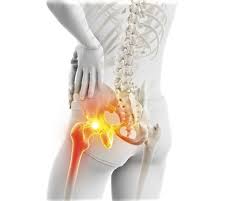

3. 고관절 통증 증상

고관절 통증은 원인에 따라 다양한 증상으로 나타날 수 있습니다.

① 사타구니 통증

고관절에 문제가 있을 경우 통증이 허벅지 안쪽 또는 사타구니 부위에 나타나는 경우가 많습니다.